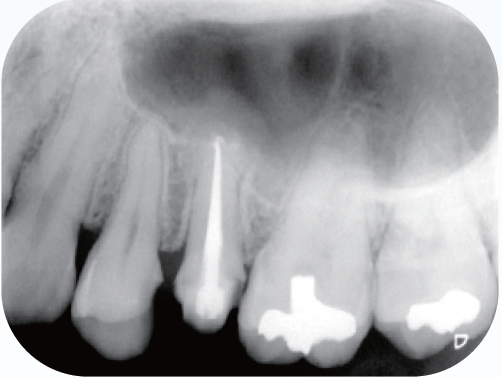

初診時のデンタルX線像を示す。レントゲン所見では根尖周囲組織に炎症を示す像を認め、その影響が上顎洞粘膜の肥厚の原因と推測されるレントゲン像である。

<症例1>●初診時年齢 31歳 女性 初診日2011/10/14

左上5番を他院で根管充填後、打診痛が消失しないので転院され受診患歯にはインレー修復がされている。根尖部は上顎洞と近接しており、上顎洞粘膜の肥厚も認められた

(症例1・①)根管充填の状態は比較的良好である。根管拡大・形成の3次元的評価のためCBCTを撮影。

CT像左上5番根尖部を中心として上顎洞粘膜の肥厚が認められ、根尖性歯周組織炎の影響が上顎洞まで及んでいると考えられた

根管処置後の修復が保存修復されて髄室開拡に制限があり、歯頸部周辺に存在する頬口蓋側に広がる髄角の形態が確認でき(症例1・②)、この部分に根管拡大不足の可能性を疑えた。根尖病変の原因として、頬口蓋的な根管拡大不足による起炎物質の取り残しによる感染が要因の一つであると診断した。より的確な予防形成を行うにあたり、器具操作の向上のため髄室開拡の修正が必要であると判断した。よって最終修復は歯冠修復による補綴修復が必要であると患者に説明し、承諾が得られたので再治療を行なった。

(症例1・②)

線で示した部分に髄角部の形態がそのまま残存していることが予測され拡大不足、未処置部分が存在すると判断した